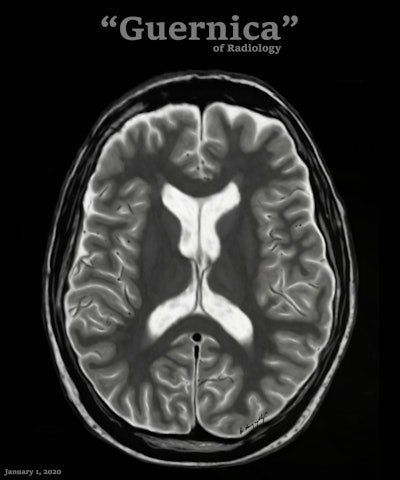

Conceptually, I think it is possible to define the term “radiological illustration” as an emerging discipline that transforms medical imaging data into an aesthetic and didactic narrative. I emphasize that with the motto “pixel by pixel handmade.” I am trying to open a “new path” for the use of visual communication in medical education by trying to combine scientific accuracy in radiological terms with artistic creativity. With this statement, I am trying to express that instead of modifying radiological images, I draw each pixel by hand using technological tools and create a new visual that is both artistically and scientifically original, while remaining faithful to radiological principles.

It’s important to note that radiological illustration should not be confused with medical illustration. The former has yet to be systematically defined in the literature. I believe it deserves recognition as a distinct sub-branch within the broader medical illustration domain.